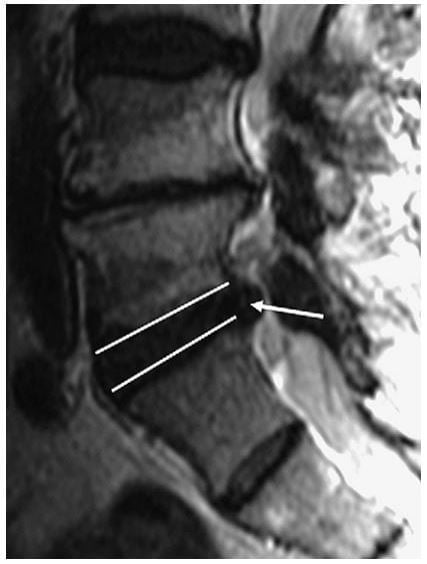

Thoát vị là protrusion nếu khoảng cách lớn nhất của các bờ chất bị lồi nhỏ hơn các bờ của chất đĩa đệm bình thường khi xác định trên cùng một mặt phẳng. Ví dụ, nếu khoảng cách trên dưới của các bờ chất đĩa đệm bị thoát vị nhỏ hơn hoặc bằng các bờ của chất đĩa đệm bình thường trên cùng một mặt phẳng (khi đo ở mặt cắt sagittal hoặc coronalđể đánh giá độ lan trên dưới), thì nó được phân loại là protrusion (Hình 3). Đo chiều trên dưới gần như luôn tốt nhất ở mặt phẳng sagittal. Lồi khu trú khi xác định trên mặt phẳng axial là phần thoát vị liên quan với ít hơn một nửa đĩa đệm (< 180 độ chu vi đĩa đệm). Protrusion có thể được phân loại thêm thành khu trú hoặc đáy rộng dựa vào mức độ đĩa đệm bị tổn thương. Protrusion khu trú liên quan với ít hơn 25% (hoặc 90 độ ) của chu vi đĩa đệm,trong khi protrusion đáy rộng nằm giữa 25% đến 50% (90-180 độ) của chu vi đĩa đệm (Hình 4).

Hình 3. Hình sagittal T2W mô tả protrusion đĩa đệm L5-S1 (mũi tên trắng). Ghi nhận chất đĩa đệm thoát vị không vượt qua giới hạn của bờ trên và bờ dưới đĩa đệm (tức là vượt qua chỗ nối đĩa đệm/bề mặt thân sống). Khi xác định trên mặt cắt sagittal, thoát vị đĩa đệm này là protrusion.